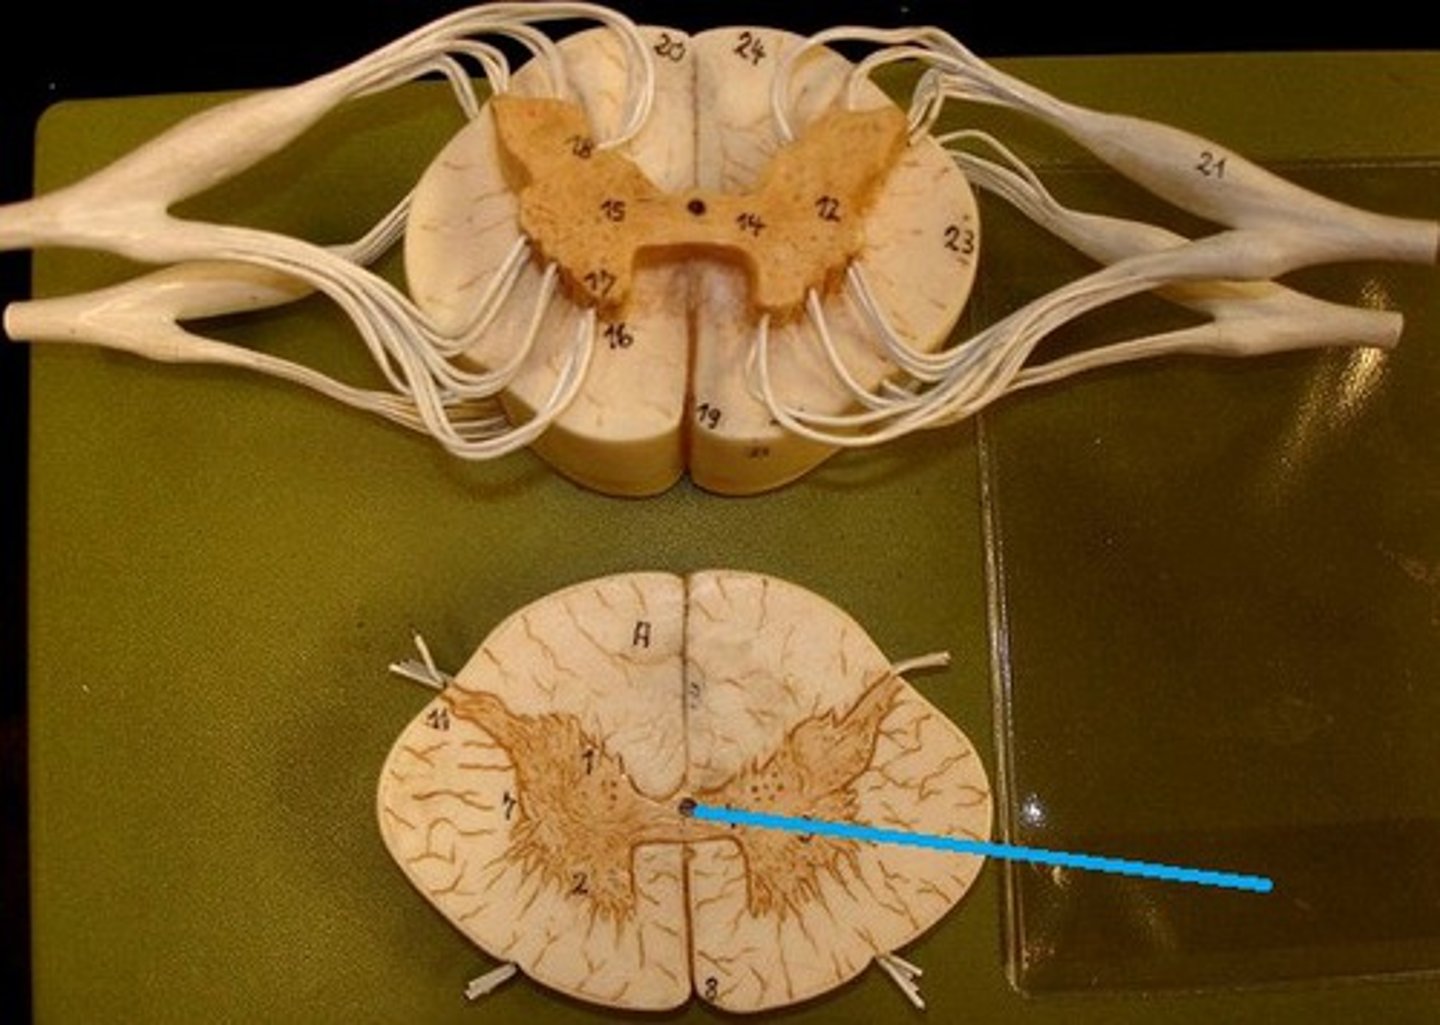

anterior (ventral) root (of spinal cord)

central canal (of spinal cord)

gray matter (of spinal cord)

posterior median sulcus

anterior median fissure

cauda equina

dorsal root ganglion (spinal)

posterior (dorsal) root (of spinal cord)

spinal nerve

white matter (of spinal cord)